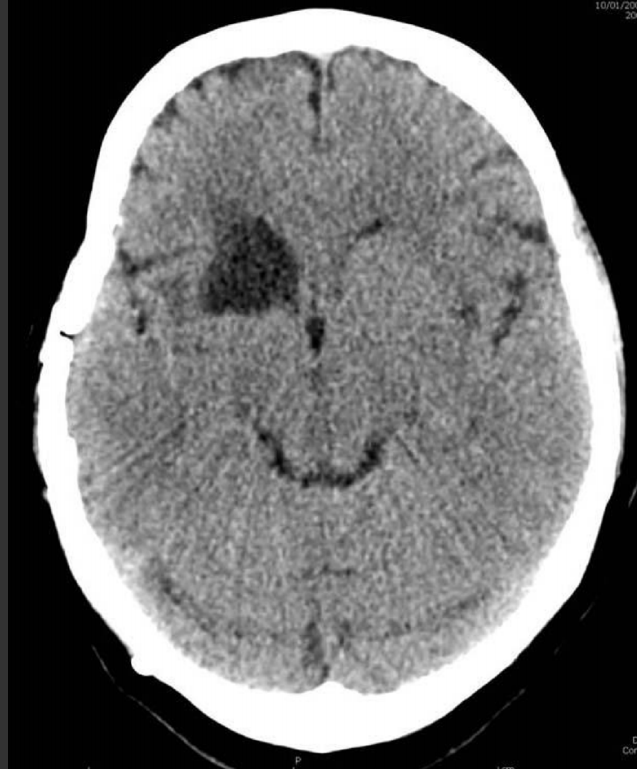

60

A 48 year-old man with a right middle cerebral artery distribution infarction. Despite aggressive medical and endovascular therapy, the artery remains occluded. Two days later he has a decline in mental status. His head CT is shown. What is the most likely explanation for the patient’s new neurological deterioration? A. Occlusive hyperemia B. Reperfusion syndrome C. Hemorrhagic conversion D. Cerebral edema E. Normal perfusion pressure breakthrough

D. Cerebral edema